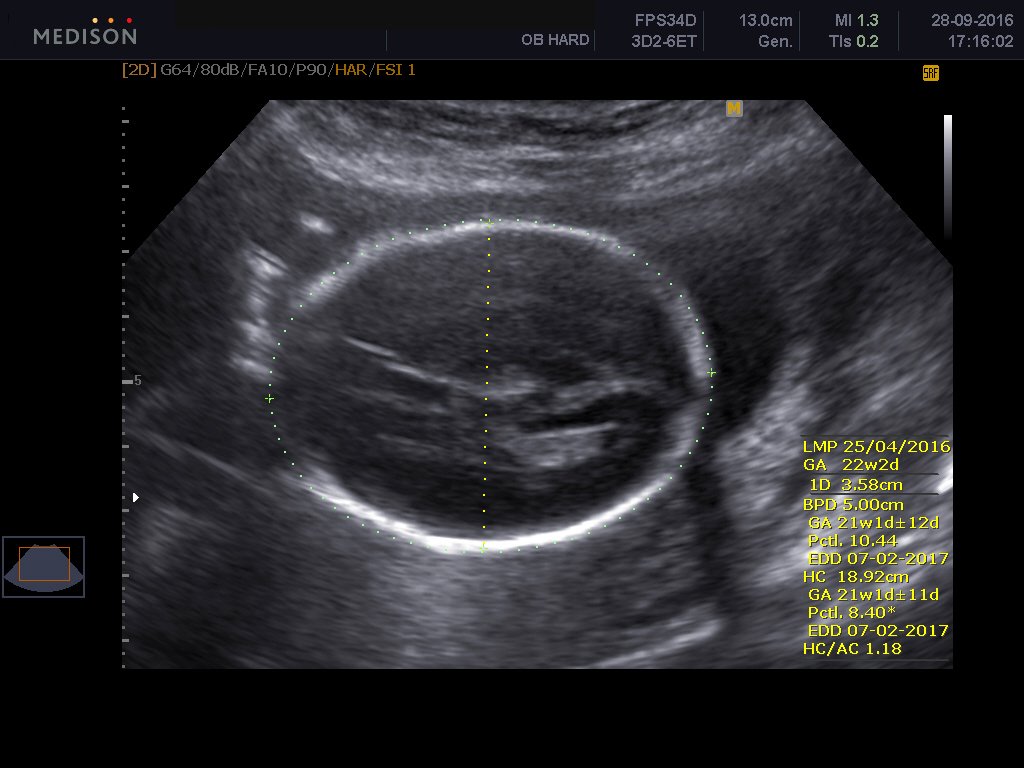

To υπερηχογράφημα β επιπέδου είναι ειδικό υπερηχογράφημα το οποίο εκτελείται από εξειδικευμένο ιατρό και με το οποίο ελέγχεται λεπτομερώς η ανατομία του εμβρύου. Γίνεται όπως όλα τα υπερηχογραφήματα δια μέσου της κοιλιακής χώρας της εγκύου και είναι απόλυτα ανώδυνο.Είναι δυνατόν το υπερηχογράφημα να απεικονίσει σοβαρές συγγενείς ανωμαλίες του εμβρύου καθώς και ελαφρές ανατομικές βλάβες. Επίσης αναγνωρίζει υπερηχογραφικά σημάδια , τα καλούμενα markers , με τα οποία υποπτευόμαστε σοβαρά χρωμοσωμιακά σύνδρομα εμβρύου, όπως το σύνδρομο Down, την trisomy 18 και trisomy 13. Γίνεται έλεγχος του πλακούντα εκτιμάται το αμνιακό υγρό καθώς και η προβολή του εμβρύου και ο τράχηλος της μήτρας και ειδικά το μήκος τραχήλου μας δίνει πληροφορίες όσον αφορούν τον πρόωρο τοκετό.

Ελέγχεται το κρανίο, ο εγκέφαλος, το πρόσωπο, η καρδιά, τα χέρια, τα πόδια, η σπονδυλική στήλη, η ουροδόχος κύστη του μωρού. Μερικές συγγενείς βλάβες που μπορεί να αναγνωρίσει το υπερηχογράφημα είναι οι εξής: Ανεγκεφαλία, ανοιχτές βλάβες νωτιαίου σωλήνα , χειλεοσχιστία -λαγόχειλος, διαφραγματοκήλη, γαστρόσχιση , εξόμφαλος, σοβαρές καρδιακές συγγενείς ανωμαλίες, αγενεσία νεφρών, πολυκυστικούς δυσπλαστικούς νεφρούς, θνησιγενείς σκελετικές δυσπλασίες.

Σύμφωνα με πανευρωπαϊκή στατιστική μελέτη η υπερηχογραφική δυνατότητα ανίχνευσης σοβαρών συγγενών ανωμαλιών ανέρχεται στο 73,7%, ενώ των ελαφρών συγγενών ανωμαλιών στο 45,7%. Υπερηχογραφικά μόνο δεν είναι δυνατόν να αποκλεισθεί η πιθανότητα χρωμοσωμιακής ανωμαλίας καθώς και όλων των συγγενών ανωμαλιών.